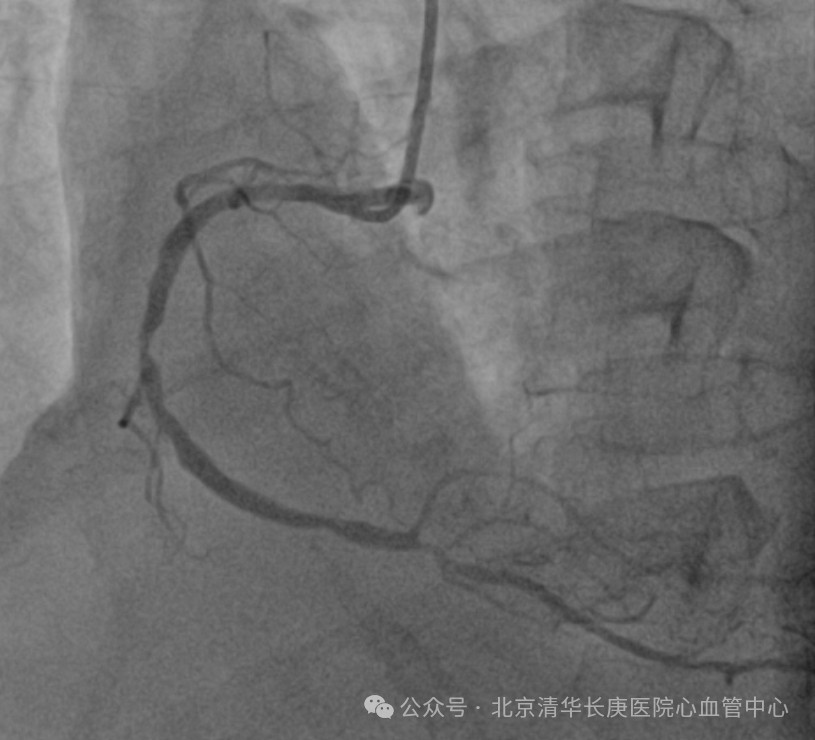

(患者冠脉造影)

故事得从2024年元旦说起,伴随着一阵急促声,北京清华长庚医院急诊部接诊了一位突发喘憋伴一过性意识丧失的患者,急诊医师快速判断出患者存在心肌缺血及心衰表现,且合并晕厥,病情危重,遂请心血管内科急会诊。北京清华长庚医院心血管内科当天值班的佘飞主任、向伟主治医师迅速到场,详细询问后发现王阿姨患有高血压,糖尿病,高胆固醇血症多年,平素间断有胸闷症状。3个月前突发过明显胸痛1次,在家休息后缓解。此后逐渐出现活动量明显下降。当天因着急追公交车后突发喘憋伴一过性意识丧失紧急就诊。佘飞主任、向伟主治医师迅速判断出王阿姨患有冠状动脉粥样硬化性心脏病(简称冠心病),3月前突发急性心肌梗死后出现心功能不全,此次因为追公交车后出现了心衰急性发作伴晕厥。冠心病 心肌梗死非常常见,心力衰竭是心肌梗死后十分常见的并发症,严重影响患者的生活质量,也是导致反复住院甚至导致死亡的常见病因。为此,王阿姨被立即护送到心血管中心接受治疗。在佘飞主任、何榕主任及马志毅副主任医师、向伟主治医师的指导下、心血管中心医护团队为王阿姨精心制定了治疗和护理方案,超声影像团队的刘芳主任医师也为患者仔细查进行了超声心动图检查证实王阿姨的心脏出现了心肌梗死后的一系列典型改变(左心增大、室壁运动障碍、室壁瘤形成、心功能显著减低,左心室射血分数仅35%)。冠脉介入团队的耿雨主治医师随后为王阿姨进行造影检查发现王阿姨的三支冠脉均严重狭窄,其中左前降支近端100%闭塞。后续检查发现其心脏梗死面积大,冬眠心肌少。优化药物治疗后王阿姨的喘憋症状得到了显著缓解,但冠脉狭窄、心肌坏死及室壁瘤无法解决。